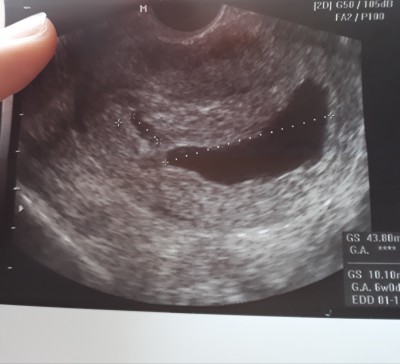

Kurtajdan sonra hemen gonderiyolarmi yarin olucamda yanima ne almam gerekiyor

Gebelik haftası 12

İnsallah cok tesekkur ederim sebebi bos gebelikmis